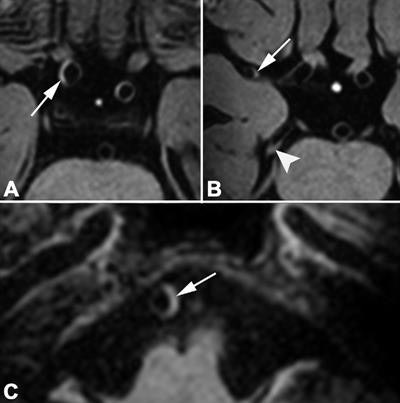

Risk factors such as hypertension, diabetes, and smoking have been associated with intracranial atherosclerosis, which accounts for 5% to 23% of ischemic strokes in the white population. While CT and MR angiography or digital subtraction angiography have been used to determine a link between intracranial calcifications, stenoses, and ischemic stroke, the modalities are limited in the evaluation of vessel wall lesions, which occur at the most advanced stage of intracranial atherosclerosis. Therefore, 3- and 7-tesla MRI have become increasingly utilized to detect the anomalies more expeditiously.

The question remains, however, as to which cardiovascular risk factors are the greatest contributors to vessel wall narrowing. In this study, Lindenholz and colleagues explored age, hypertension, gender, high or low levels of fat and lipids in the blood, and other influencers and their relationships to vessel wall lesions (Radiology, April 2020, Vol. 295:1, pp. 162-170).

In correlating 7-tesla MR images of lesions with the risk factors, the researchers discovered three conditions that contributed most significantly to atherosclerotic lesions and stroke with anterior circulation vessel wall lesions: